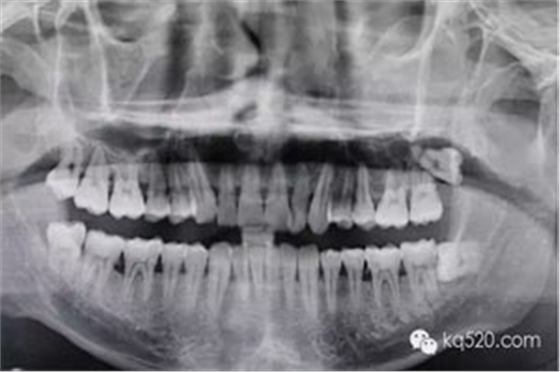

圖3.全景片影像檢查:28牙根似乎位于上頜竇內(nèi),拔除28要注意上頜竇瘺。